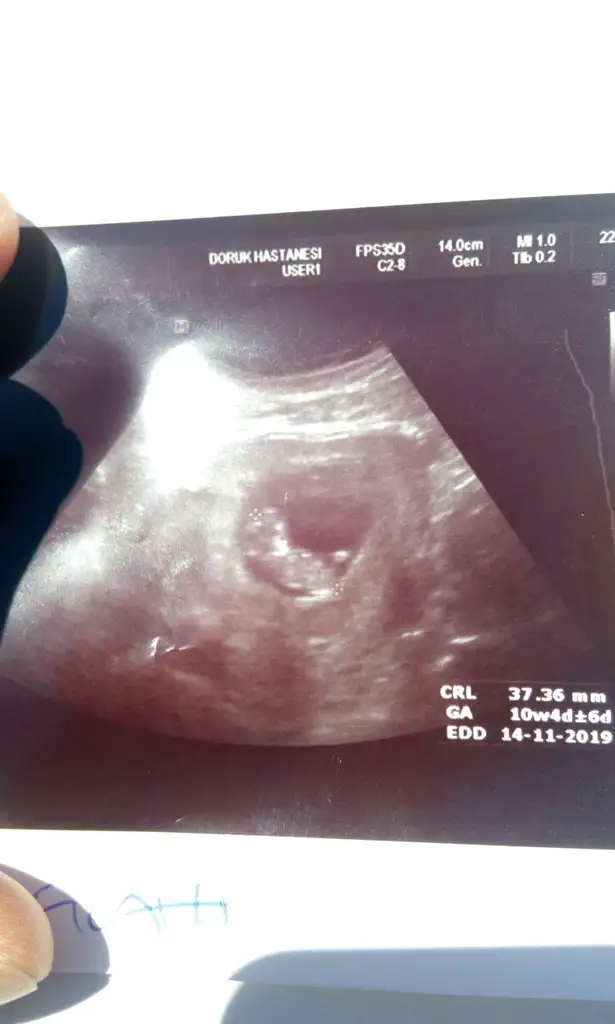

iyi gözün aydın canım :)benim bu defaki usg kağıdımın yanında crl ve haftası yazmıyor crl yi merak ediyorumÖzele gittim canım,bi sıkıntı yok şükür

37.36 mm olmuşkorkup kasılmışsın dedi doktor.